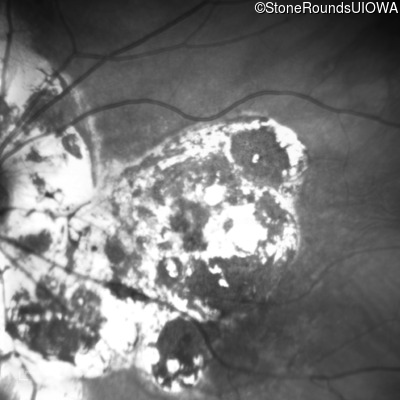

Blue Autofluorescence - Left - 10/140

Exemplar